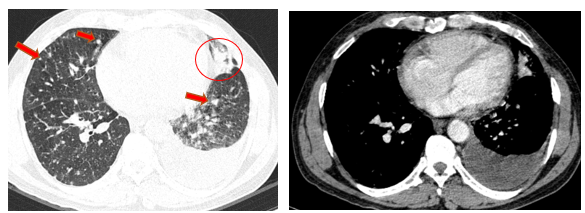

- Chụp cắt lớp vi tính lồng ngực (08/2025): Khối rốn phổi trái ôm quanh nhánh phế quản thùy dưới trái kích thước 28x26mm, dày tổn chức kẽ vách liên tiểu thùy và nhiều nốt đặc lan tỏa khắp nhu mô, đường kính <7mm. Màng phổi trái có vài nốt đặc ngấm thuốc nốt lớn nhất kích thước 17x15mm Khoang màng phổi trái có dịch dày 54mm. Nhiều hạch to trung thất, rốn phổi hai bên và hố thượng đòn có hoại tử trung tâm, hạch lớn nhất kích thước trục ngắn 22mm.

Hình 01: Nhiều hạch to trung thất, rốn phổi hai bên và hố thượng đòn có hoại tử trung tâm, hạch lớn nhất kích thước trục ngắn 22mm

Hình 02: Khối rốn phổi trái ôm quanh nhánh phế quản thùy dưới trái kích thước 28x26mm, dày tổn chức kẽ vách liên tiểu thùy và nhiều nốt đặc lan tỏa khắp nhu mô, đường kính <7mm.

Hình 03: Màng phổi trái có vài nốt đặc ngấm thuốc nốt lớn nhất kích thước 17x15mm Khoang màng phổi trái có dịch dày 54mm